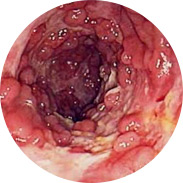

I principi attivi in modo completo, rafforzando l'azione dell'altro, eliminano i principali sintomi delle emorroidi:

• Sanguinamento durante la defecazione o una mescolanza di sangue nelle feci

• Nodi prolassati dal retto

• Sensazione di corpo estraneo, sensazione di pesantezza

• Prurito e bruciore nella zona dell'ano

• Dolore alla defecazione, camminando e stando seduti